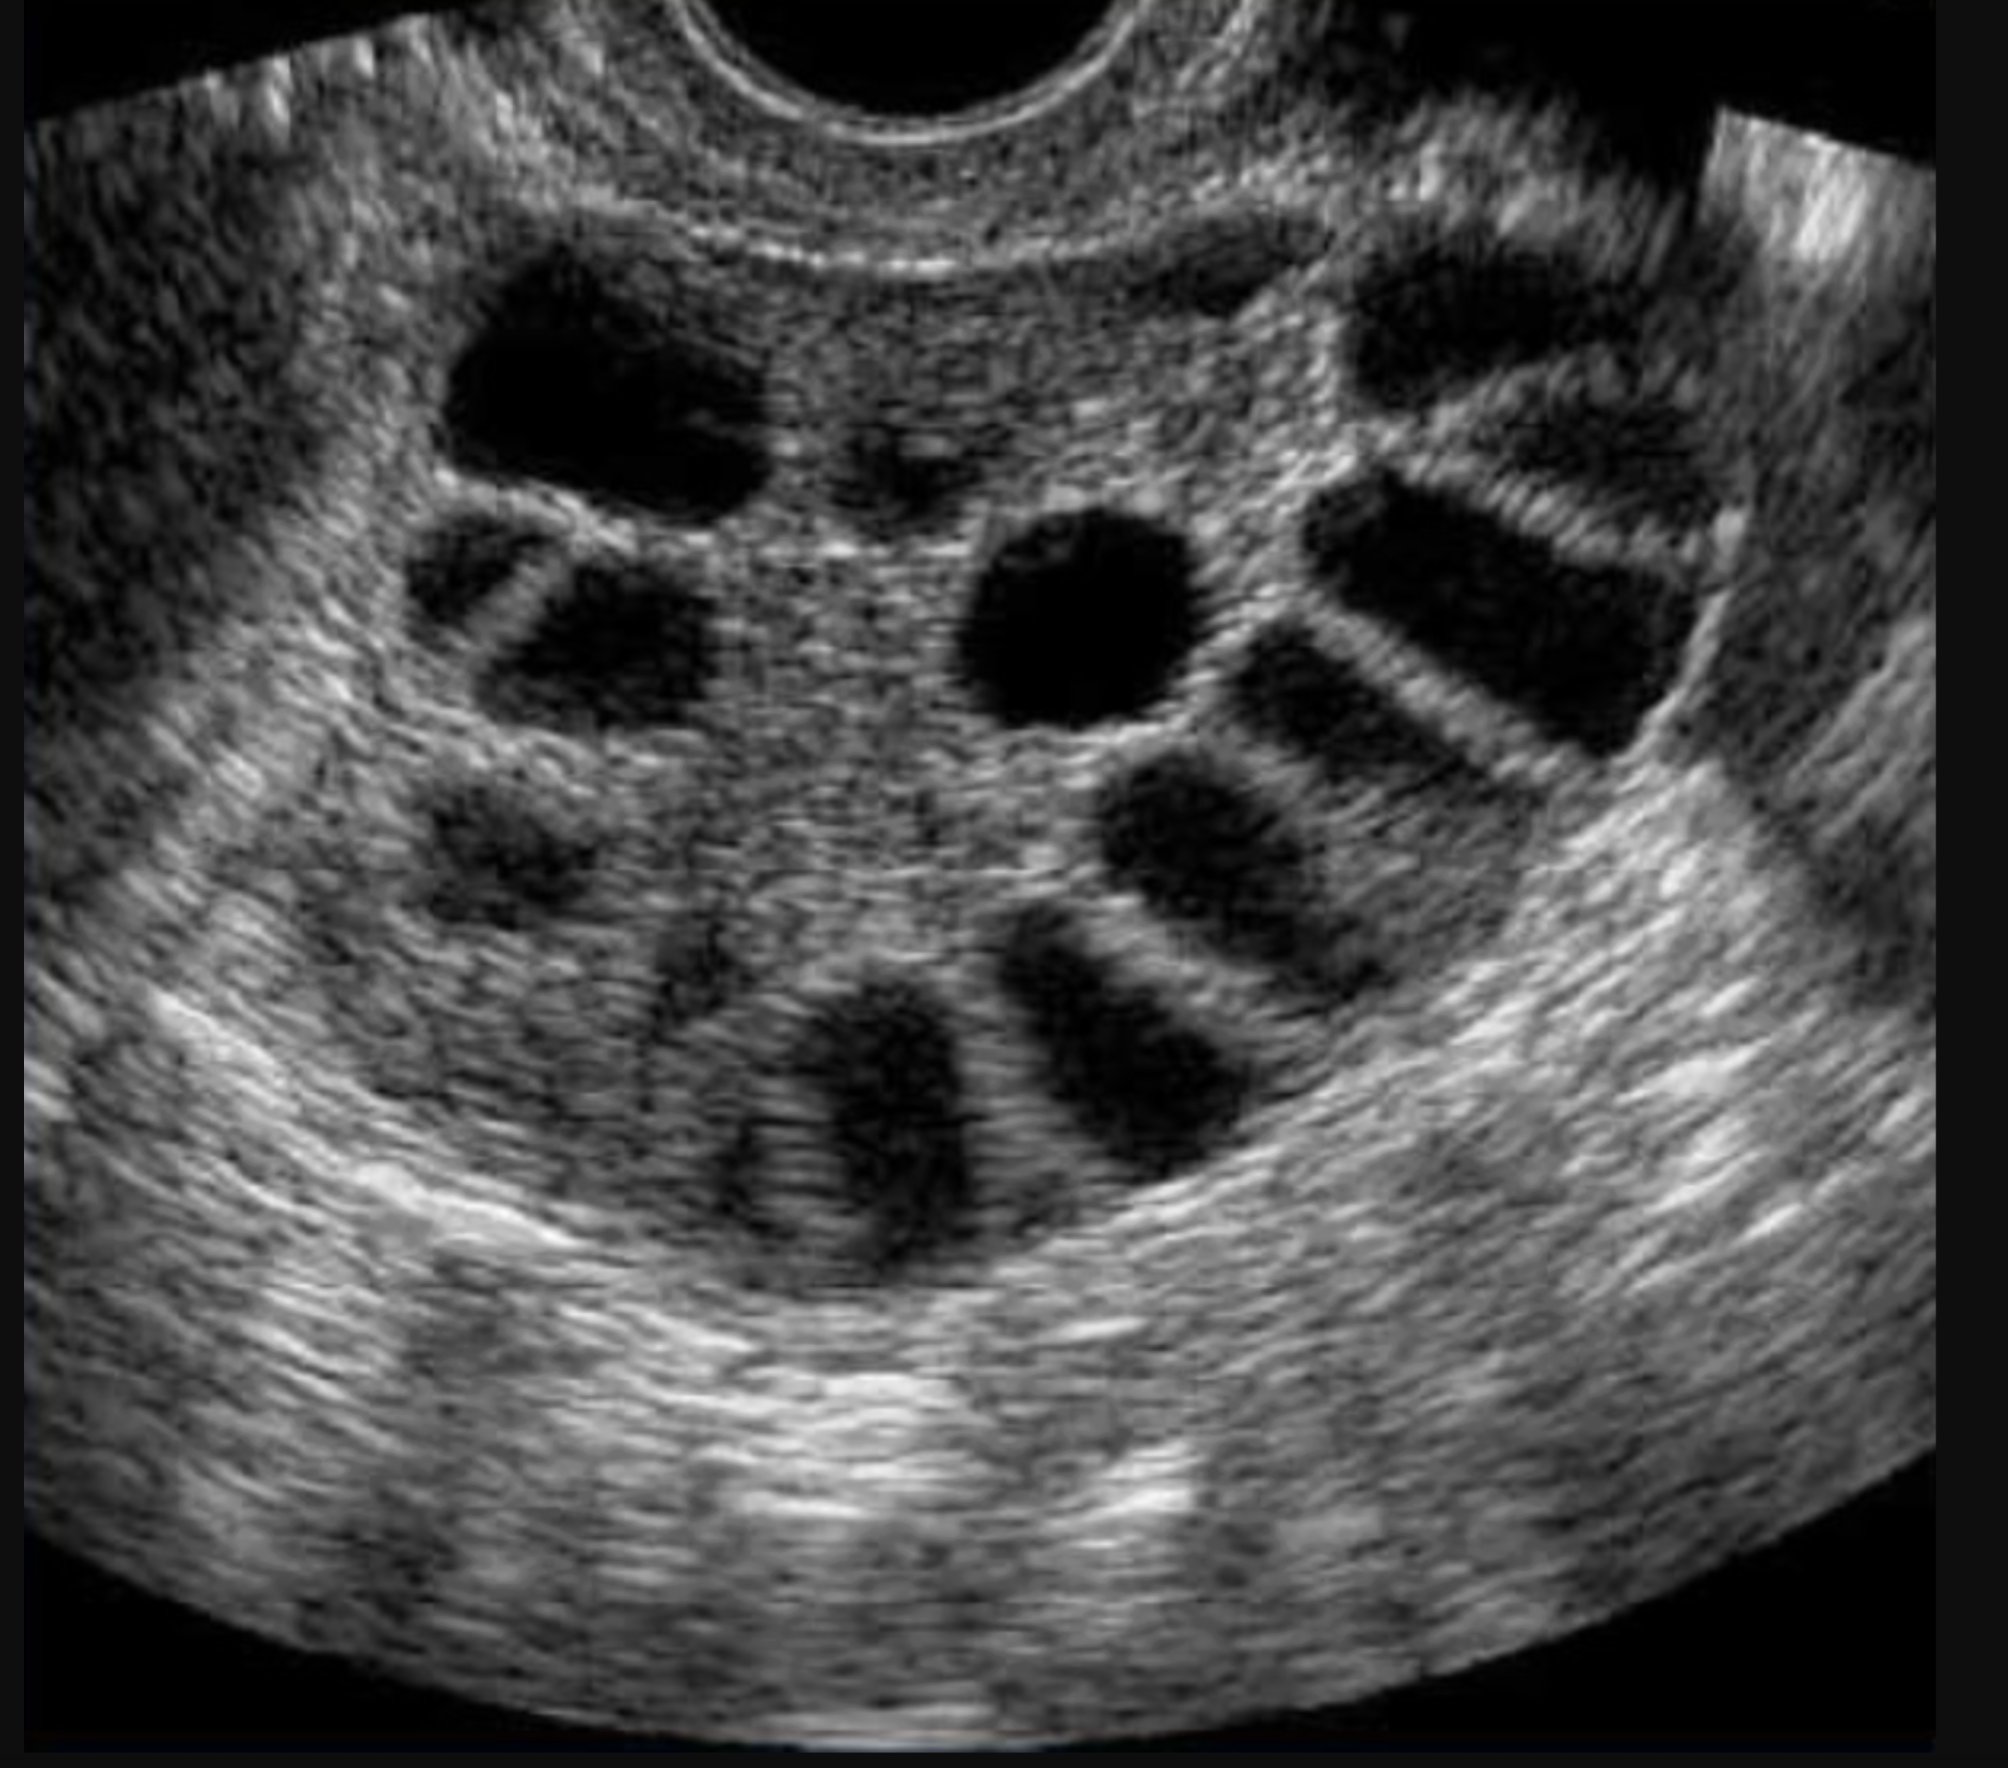

En algunas mujeres que sufren este trastorno, los ovarios pueden verse agrandados y con numerosos folículos pequeños que no han alcanzado la maduración necesaria, esto se conoce comúnmente como el aspecto de “collar de perlas”.

Ciclos sin ovulación: Cuando el folículo no logra madurar y romperse, como consecuencia no se libera un óvulo, por lo que con el tiempo, estos folículos inmaduros permanecen alrededor del ovario y se van acumulando.